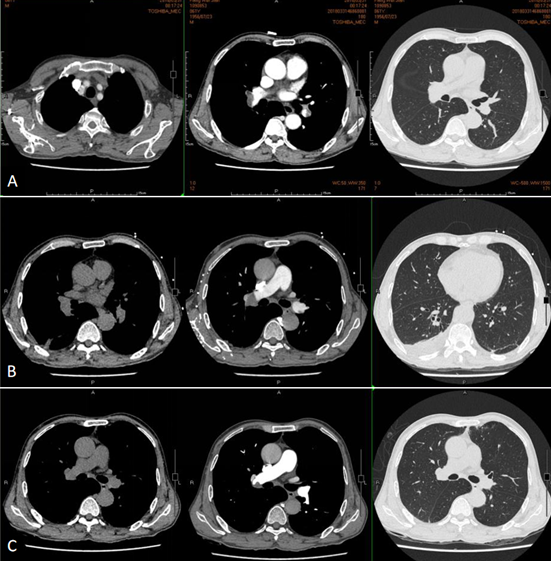

• 电子支气管镜:气管及双侧四级以内支气管管腔通畅,黏膜无充血、水肿、糜烂,未见新生物、异物及活动性出血(图3)

图3  患者电子支气管镜检查

注:左图隆嵴,右图左上叶和舌叶开口,支气管管腔通畅,黏膜无充血、水肿、糜烂